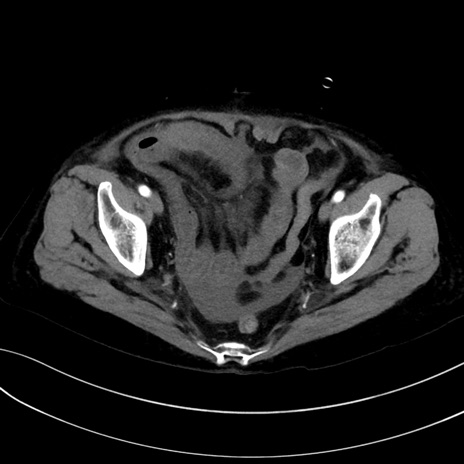

(冠状断像)1日半後